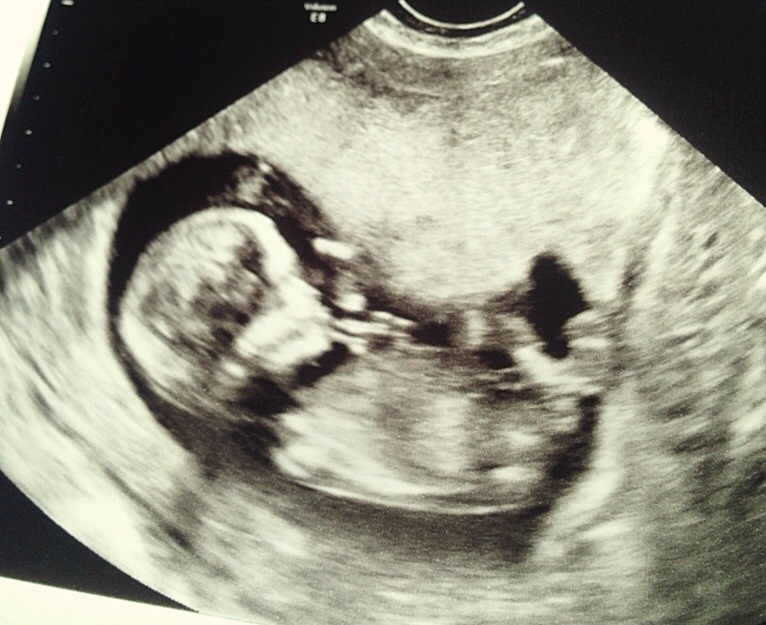

Hi ladies! I just found this site today and I'm so excited and wish I would have found it sooner!! I have a few pictures I'm going to try and upload, one is from my Dr at 12w5d just to show the skull and nub theory, I'm not great about that but just maybe to help. Lol the next is at 13w5d from an elective scan I had to try and see the gender. They leaned towards girl but I'll confirm with my actual Dr sep 5th, it's killing me waiting though! I've had mixed reviews from everyone I've shown! Some say girl, some say boy, some say to keep receipts of I buy pink.... It's so confusing! I wouldn't be so doubtful I think had so many people question the scan, and the fact it took forever to even get a hint! Baby was stubborn! It was supposed to take 15 minutes, took 45.... Two techs.... Me having to get up and move around multiple times. Lol it was a show!

I'm thinking this probably should have been done on my laptop now. I can't organize them very well on my phone, the side view on 2d was at 12w5d everything else like the 3d and between the leg shots were all taken 13w5d I hope that makes sense!